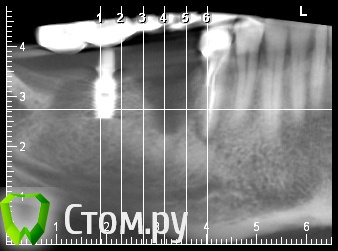

Dc.Petrov Опубликовано 16 января, 2014 Поделиться Опубликовано 16 января, 2014 Пришел пациент из другой клиникиИмпланты установлены 2 года назад, принес в руках мост с "торчащим" из него имплантом.Со слов болей никаких не было, просто расшаталось все и выпало. Слева отсутствуют 25,26,27Вопрос:1.почему?2. что делать?Мои размышления: Возможные причины- остутствие ЗКПД и соседний "не оч здоровый" зуб+ перегрузкаплан: удаление 45, кюретаж костного дефекта, графт + мембрана, через 4-5 месяцев имплантация 46,45. Ну и с десной поработать перед протетикой.Выскажите свое мнение, пжста, доктора... Ссылка на комментарий

kriokov Опубликовано 16 января, 2014 Поделиться Опубликовано 16 января, 2014 Пришел пациент из другой клиникиИмпланты установлены 2 года назад, принес в руках мост с "торчащим" из него имплантом.Со слов болей никаких не было, просто расшаталось все и выпало. Слева отсутствуют 25,26,27Вопрос:1.почему?2. что делать?Мои размышления: Возможные причины- остутствие ЗКПД и соседний "не оч здоровый" зуб+ перегрузкаплан: удаление 45, кюретаж костного дефекта, графт + мембрана, через 4-5 месяцев имплантация 46,45. Ну и с десной поработать перед протетикой.Выскажите свое мнение, пжста, доктора...1. Может короткие и широкие имплантаты , установленные на треть вестибулярно почти поднадкостнично2. удалил бы 45, и имплантат оставшийся, одномоментно и в обл 46 и удаленного имплантата НКР через 4-5 мес имплантацияМожно и одномоментно установку имплантатов с удалением и нкр рассмотреть, до канала там хорошее расстояние Ссылка на комментарий